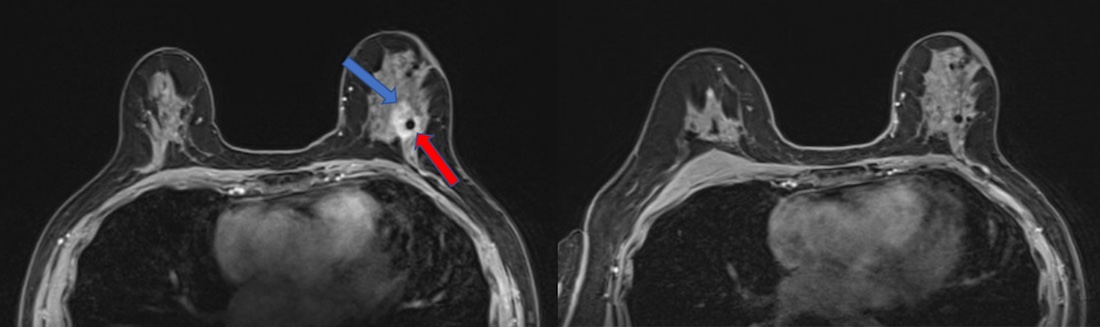

These two magnetic resonance imaging (MRI) scans were taken 10 months apart. On the left, the blue arrow points to the edge of a breast tumor, and the red arrow locates a biopsy clip, which appears as a black dot. The MRI on the right, which includes the biopsy clip, shows the tumor is gone after a single, targeted dose of radiation and antihormone therapy.

Early-stage, hormone-positive breast cancer accounts for 60%-75% of all breast cancers. Seeking a more time-efficient way to treat these patients, Dr. Rahimi and her colleagues tested a strategy in which 44 patients started treatment with a single dose of targeted radiation. While typical radiation therapy protocols call for 1.8-2.67 Gy (a measure of radiation strength) per day for 16 to 33 days, the researchers divided the study participants into three groups and gave each patient a single dose of 30, 34, or 38 Gy. The volunteers then went on hormone-blocking drugs and waited a median of 9.8 months until they underwent surgery to remove any residual tumor tissue.

In 72% of study participants, the surgeons found no residual tumor left, indicating that patients had a “pathological complete response.” An additional 21% of patients had a “near complete response,” meaning that their cancer was more than 90% eliminated.

When the researchers further analyzed the results, they found that time to surgery was the best predictor of response. The longer patients waited to undergo surgery, the more likely their tumors were to disappear, regardless of the radiation dose or tumor size. These results were probably due to the time it takes cells to die or be removed by the immune system after radiation therapy, Dr. Rahimi explained.